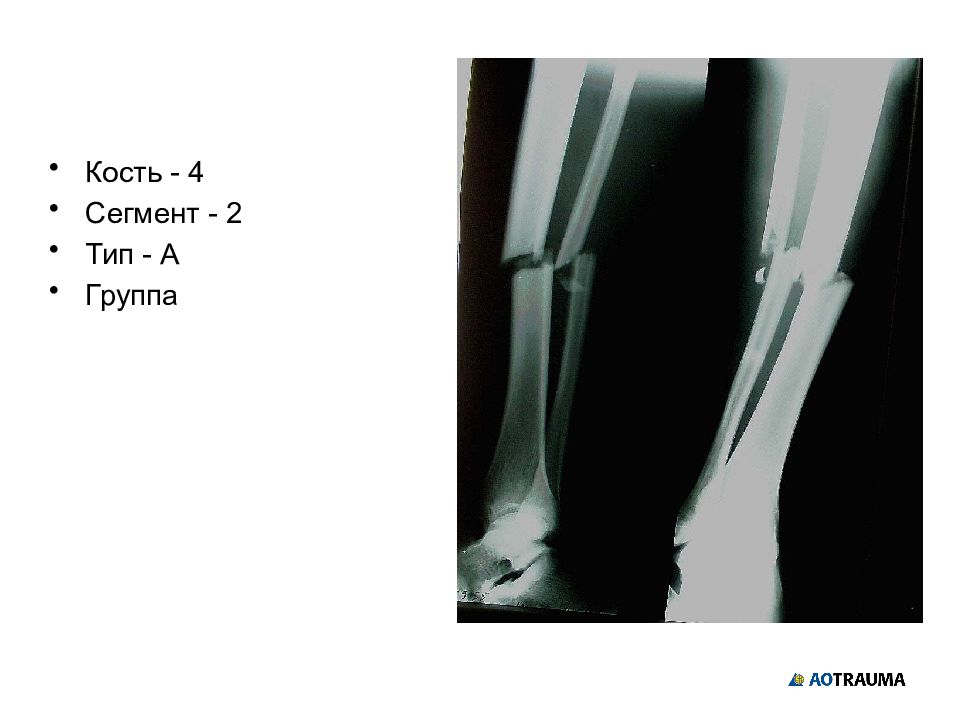

Слайд 28

Кость - 4 Сегмент - 2 Тип - А Группа